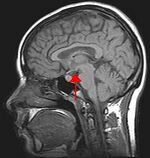

MRI depicting the human brain. The arrow indicates the position of the hypothalamus.

Biological psychology is the scientific study of the biological substrates of behavior and mental states. Seeing all behavior as intertwined with the nervous system, biological psychologists feel it is sensible to study how the brain functions in order to understand behavior. This is the approach taken in behavioral neuroscience, cognitive neuroscience, and neuropsychology. Neuropsychology is the branch of psychology that aims to understand how the structure and function of the brain relate to specific behavioral and psychological processes. Neuropsychology is particularly concerned with the understanding of brain injury in an attempt to work out normal psychological function. Cognitive neuroscientists often use neuroimaging tools, which can help them to observe which areas of the brain are active during a particular task.